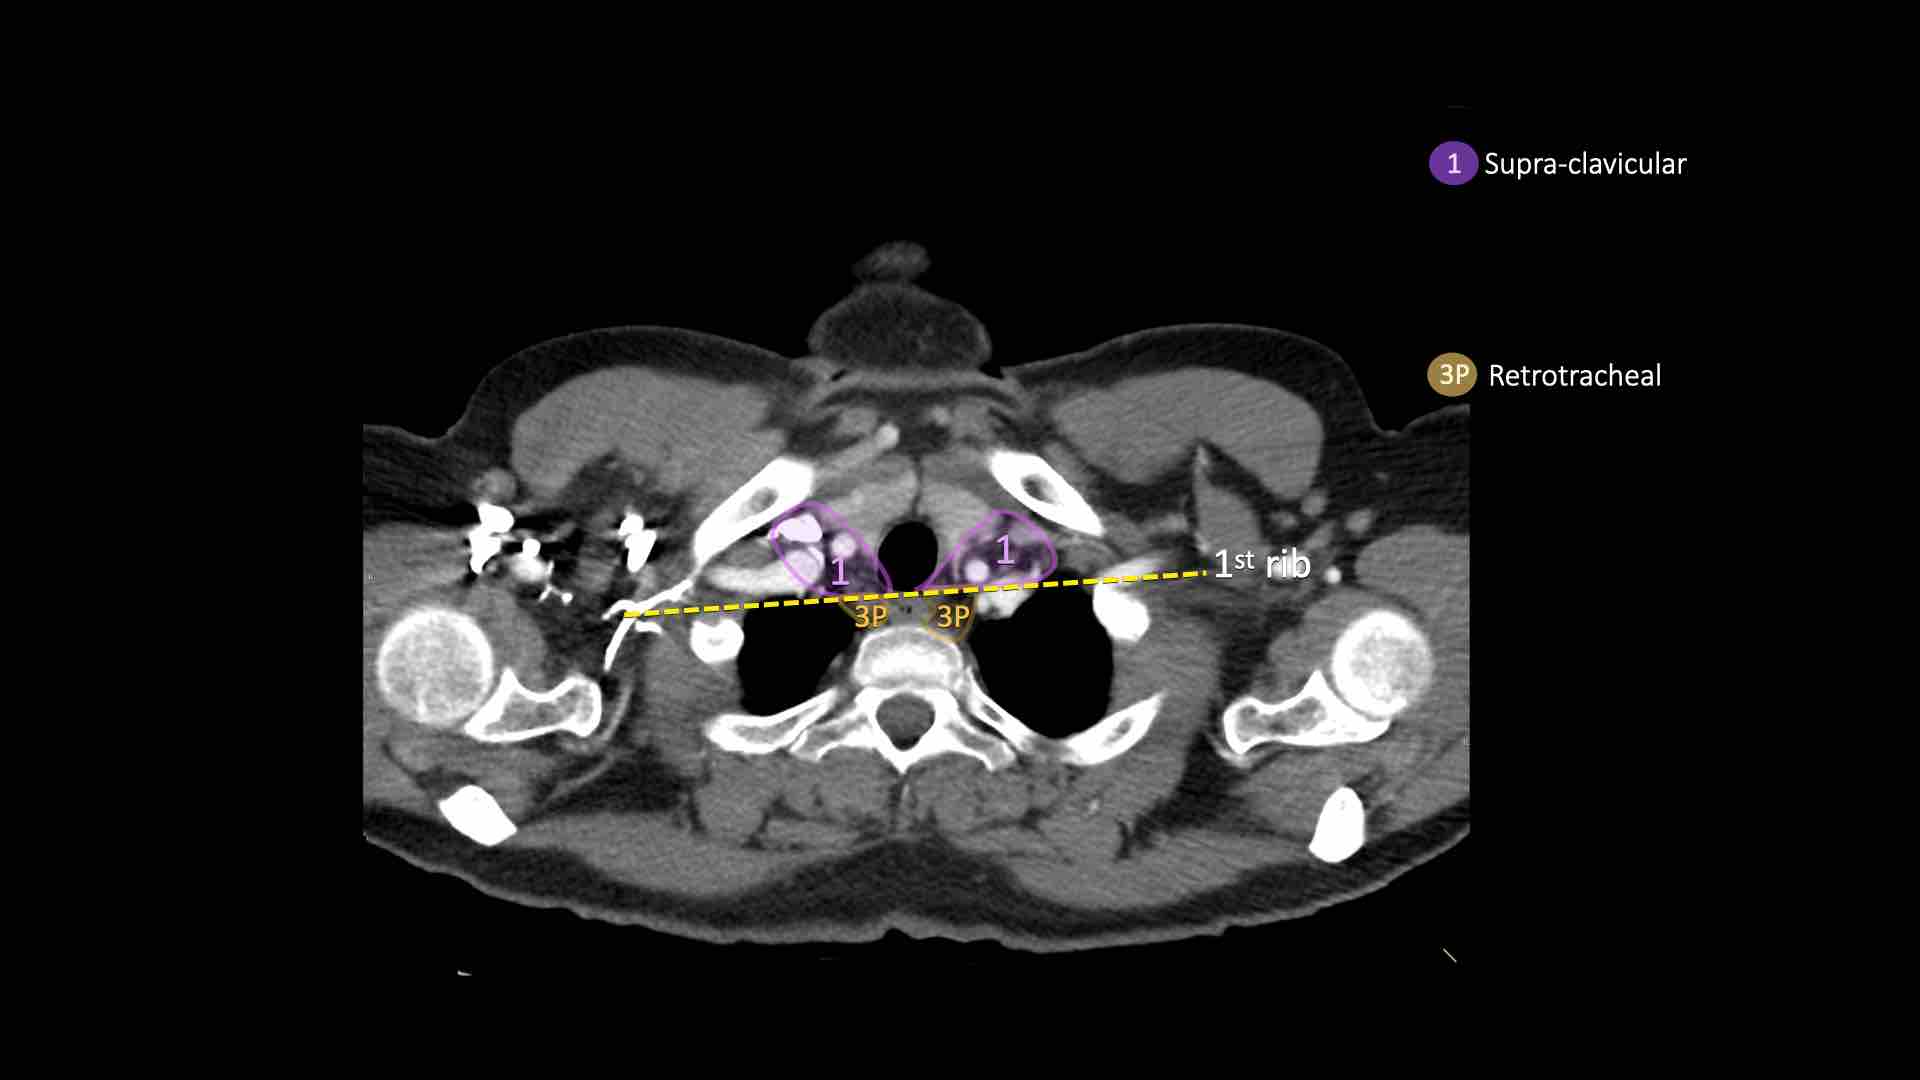

3P.Trước cột sống

Các hạch không tiếp giáp với khí quản như các hạch ở nhóm 2, mà nằm sau thực quản, tức là ở vị trí trước cột sống.

1. Hạch vùng thượng đòn

Bao gồm các hạch cổ thấp, thượng đòn và hạch khuyết ức.

Ranh giới trên: bờ dưới sụn nhẫn.

Ranh giới dưới: xương đòn và bờ trên cán ức.

Đường giữa khí quản là ranh giới phân chia giữa nhóm 1R và 1L.

3. Hạch trước mạch máu và trước cột sống

Hạch nhóm 3 không nằm kề khí quản như hạch nhóm 2.

Chúng có thể là:

3A nằm phía trước các mạch máu, hoặc

3B nằm phía sau thực quản, vốn nằm ở vị trí trước cột sống.

Hạch nhóm 3 không thể tiếp cận bằng nội soi trung thất.

Hạch 3P có thể tiếp cận bằng siêu âm nội soi (EUS).